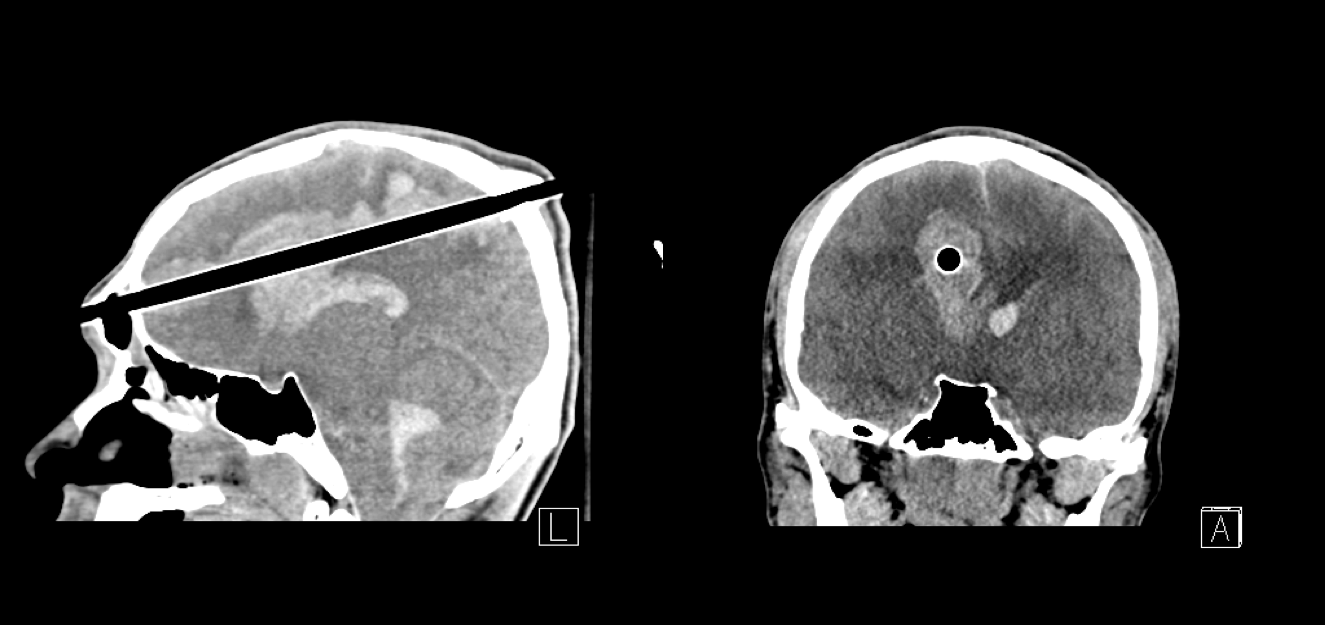

Patient presenting GCS of 6 underwent a right side hemicraniectomy

Patient presenting GCS of 6 underwent a right side hemicraniectomy Discuss What Is Meant By Hemicraniectomy A large ischemic stroke that is starting to swell is one of the most alarming situations faced by. Why would you need one?. a craniectomy decreases intracranial pressure (icp), intracranial hypertension (icht), or heavy bleeding. what is a decompressive craniectomy? a craniectomy is a type of major brain surgery where a surgeon removes part of your skull. Discuss What Is Meant By Hemicraniectomy.